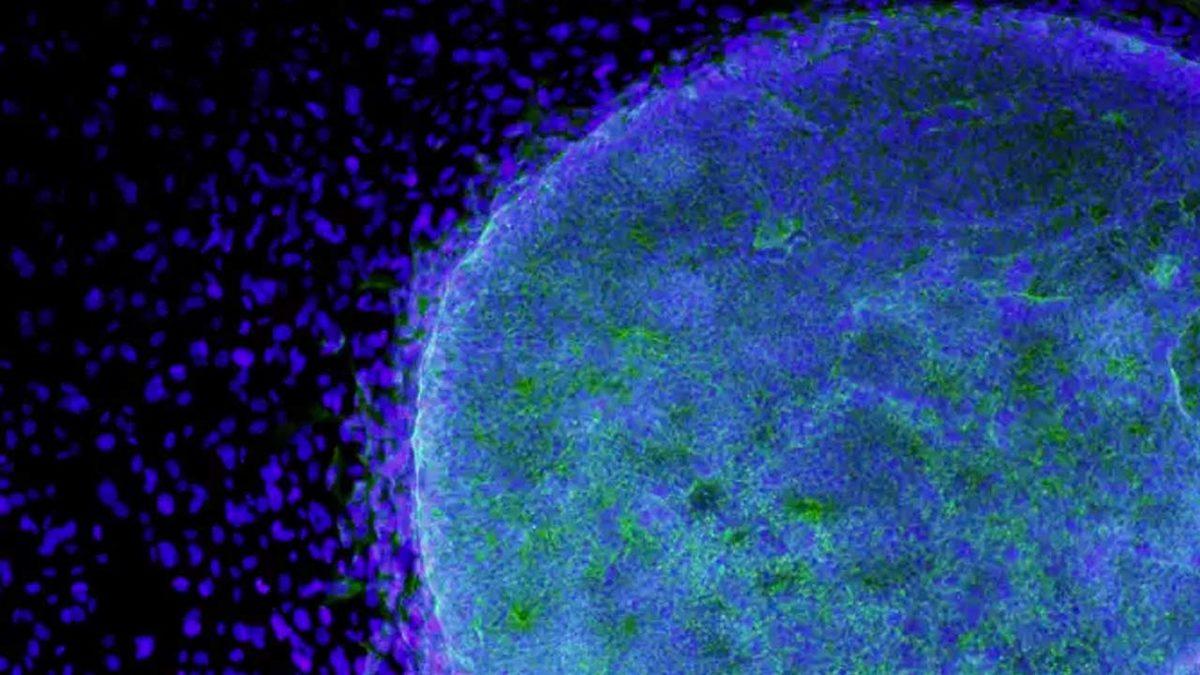

Kromozomu değiştirilen erkek farenin deri hücreleri, ‘oosit’ adı verilen, henüz olgunlaşmamış yumurta hücrelerinin oluşturulması için kullanıldı. Fakat bu süreç oldukça meşakkatliydi.

X ve Y kromozomlarına sahip bu hücreler yeniden programlanarak ‘pluripotent’ kök hücrelere dönüştürüldüler. Bir diğer deyişle hücreler, herhangi bir hücre türüne dönüşebilen hücreler oldu.

Bir sonraki aşamada ise bu hücrelerde bulunan Y kromozomu tamamen ortadan kaldırıldı, X kromozomları kopyalandı. Bu hücreler, daha sonrasında birer yumurta hücresine dönüştürüldü.